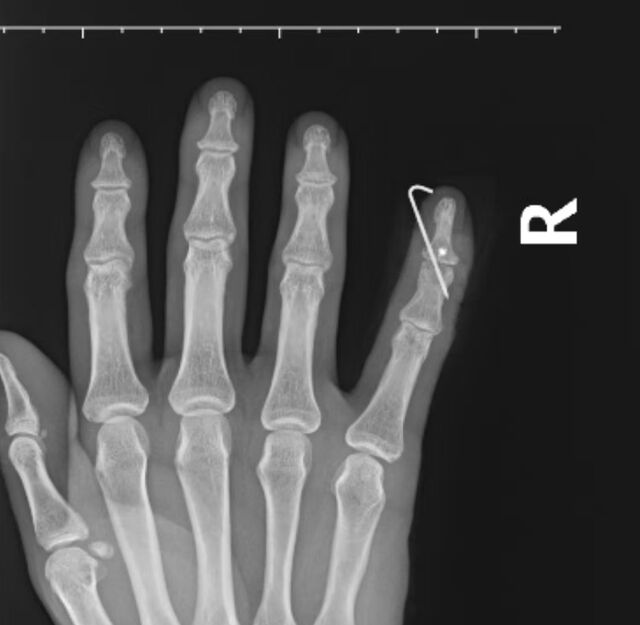

今天下午到省三院做了1台锤状指翻修手术。患者是三院内科的1名年轻医生,已经做过两次手术了,用了金属锚钉,再次复发4年了。

依然应用手套止血带法,采用“H”形切口,完全显露伸肌腱I~II区,术中见伸肌腱完全瘢痕化与中节背侧皮肤、中节指骨背侧粘连非常严重,分不清层次,而且伸肌腱侧束在近节指骨头处向两侧滑脱分离,这个病例是我做过的锤状指病例中(300余例)最严重的。最后决定取掌长肌腱游离移植。固定DIP关节于伸直位,克氏针从末节侧方进针斜行固定关节(这样固定的优点我稍后讲解),先切除伸肌腱瘢痕部分,把近侧滑脱的侧束充分松解后,拉向中线,用5-0普里灵缝线8字缝合一针,移植肌腱约1.8cm。远端端缝合,采用5-0普里灵缝线连续缝合,近端与侧束连续缝合,然后再把移植的掌长肌腱劈成两股,分别与两个侧束间断缝合。最后闭合伤口,近侧的舌形瓣长约1.5cm,而且远端很薄,血运还可以。由于4年的锤状指,背侧皮肤已被拉伸臃余,正好切除多余的近侧舌形瓣最远端皮条约3mm宽。油纱敷料包扎,铝板固定。

克氏针斜行固定DIP关节与垂直贯穿固定有3个优点:

1,进针点比末节指骨尖端宽大,容易进针。

2,不会误穿到甲床下,损伤甲基质,引起甲板畸形或者甲根坏死。

3,克氏针针尾留在指侧方,比留在指端安全,减少不慎勾住衣物拔出的风险。

术中白主任也同意我的观点,他还提出另外一个优点,就是

4,一旦出现断针,针尖部分也可以从侧方取出来,因为大多数情况是克氏针穿透中节指骨两层皮质,从指侧方出来的。

微信截图_20250826174438.png

微信图片_20250826174508.png